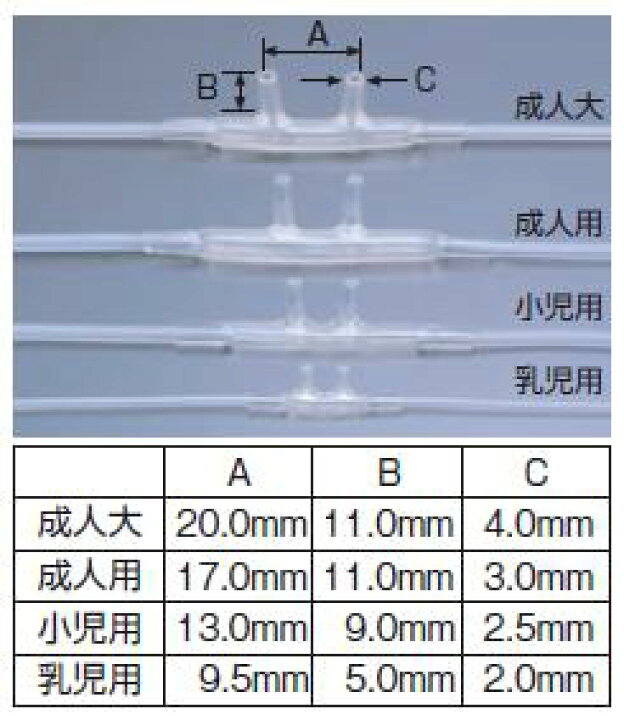

鼻腔カニューラ泉工医科工業株式会社PDNレクチャ。

アトム酸素鼻孔カニューラ OX-20 28医用ディスポーザブル製品製品情報アトムメディカル株式会社。

アトム酸素鼻孔カニューラ。

鼻腔カニューラ泉工医科工業株式会社PDNレクチャ。

アトム酸素鼻孔カニューラ OX-20 28医用ディスポーザブル製品製品情報アトムメディカル株式会社。